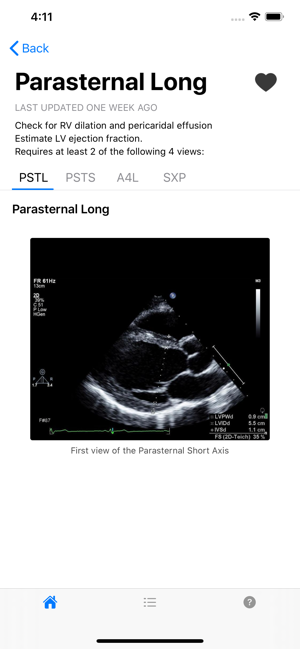

The premiere ultrasound app for minimal imaging criteria. Developed by the University of Miami Miller School of Medicine.

This application is only intended for educational and research purposes. Health care providers should use independent judgment when using this application for any purpose other than education and research. Non-medical personnel should seek a physician’s advice in addition to using this app and before making any medical decisions.